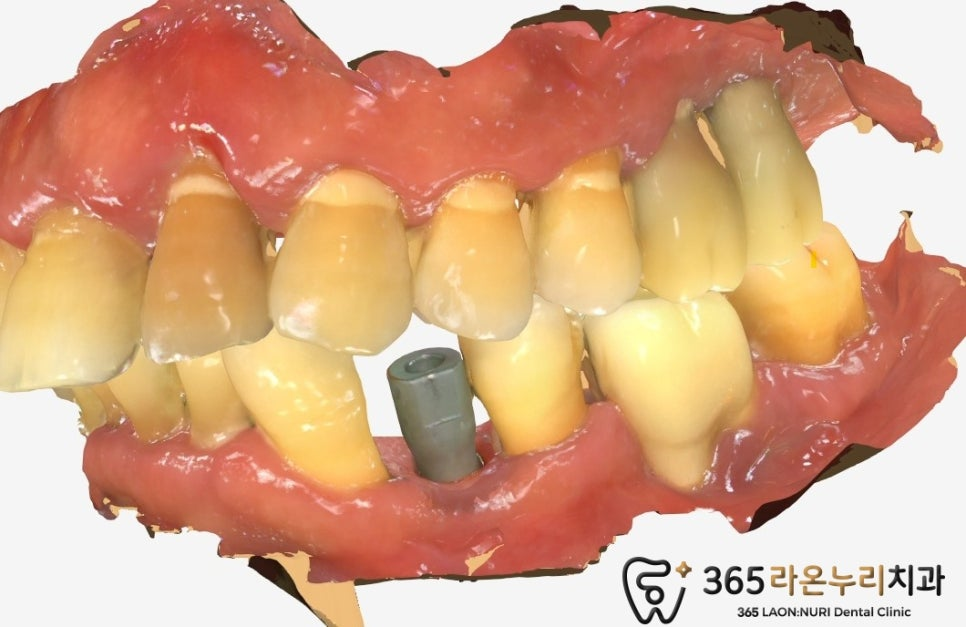

2025.04.23

식립 후 3달 뒤 ISQ를 측정하여

안정적인 수치가 나왔을 때

인상채득을 진행하게 됩니다.

2025.04.30

최종 완성된 보철을 체결하고, 교합과 표면을

주변 치아와 유사하게 맞춰주면 종료됩니다!